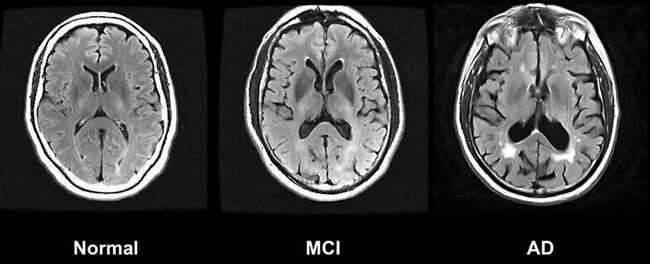

출처 : 한겨레 링크 : https://v.daum.net/v/20250716093627312 요약 : 신경퇴행성 질환은 전 세계의 약 6900만명이 앓고 있으며 매년 증가할 것으로 예상되어 전세계적인 보건 문제로 여겨져왔다. 국제 공공-민간 연구협력기관인 ‘글로벌 신경퇴행성 단백질체학 컨소시엄’(GNPC)은 2억5000만건 이상의 측정값이 포함된…